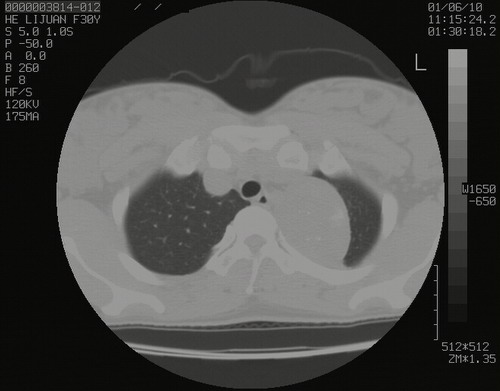

怀孕3个月时(2009-3至4月间),自述突感左侧前后胸疼痛1天,以前胸明显,随后偶感闷痛,余未见异

左肺尖脊柱旁沟肿块,境界清楚,边缘光滑,密度不均,内有多发点片状钙化,考虑良性肿瘤,骨软骨瘤或神经源性肿瘤可能,肺错构瘤不除外。

左后上纵隔见一类圆形肿块影,外侧边界清,密度不均匀,内可见点状钙化影,增强呈不均匀强化,考虑神经源性肿瘤可能。期待病理结果。